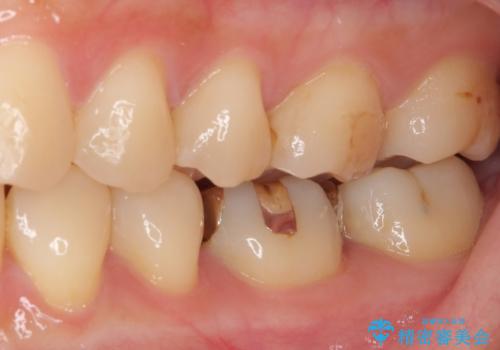

- 下の奥歯(右下7・左下7)にあって目立ってしまう銀歯を白くしたいとのことで来院された患者様です。

セラミックインレーにて修復治療を行うこととしました。

セラミックインレーを装着したことで、とても自然な仕上がりとなりました。

患者様も大きく口を開けても気にならなくなった、大変喜んでくださいました。